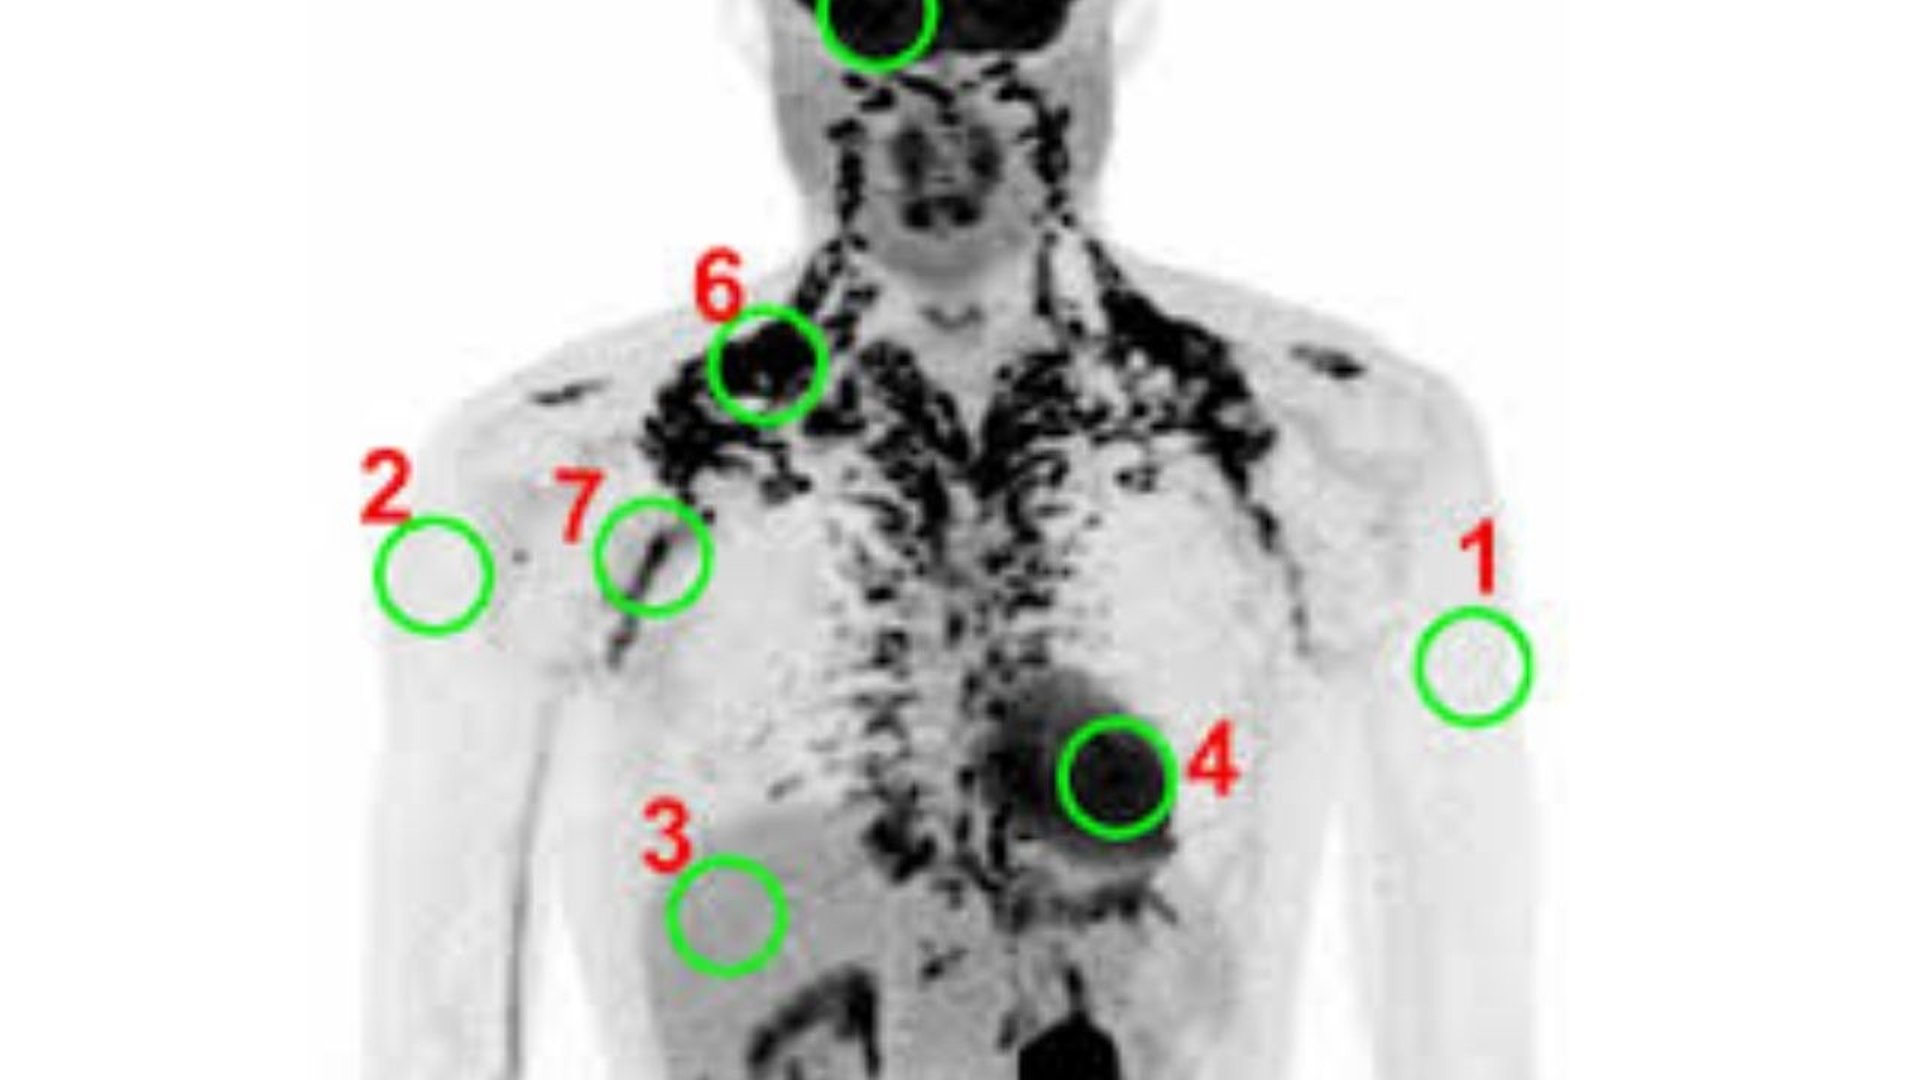

The ¹⁸F-FDG PET-CT scan has been a common method for assessing BAT.

When BAT is active, it uses up glucose, which is marked by the radioactive FDG tracer to show where the BAT is.

1. Xenon-Enhanced CT (Xe-CT): A More Accurate Option

Xenon-Enhanced CT is a big jump forward.

Recent studies that compared it directly with PET/CT suggest that Xe-CT could be more accurate for measuring BAT.

Since BAT has many blood vessels, it absorbs inhaled xenon gas rapidly.

This provides a strong signal that measures how well the tissue is functioning.